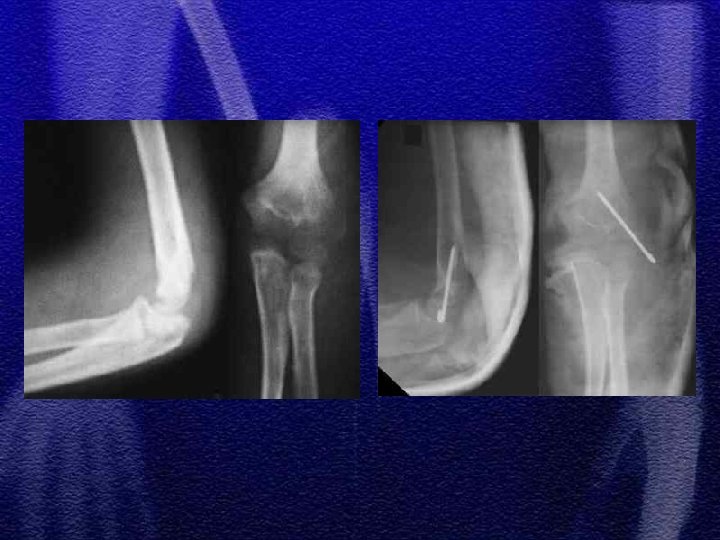

1. Jest to typ IV według Saltera-Harrisa 2. Mięśnie prostowniki, więzadło poboczne stawu łokciowego przemieszczają złamanie (złamanie awulsyjne) 3. Leczenie I° zachowawcze 4. II i III° operacyjne 5. Z uwagi na możliwość wtórnego przemieszczenia odłamów decydując się na leczenie zachowawcze należy pamiętać o kontrolach rtg. w 3, 7, 14 dobie od złamania

§ Występuje znacznie rzadziej aniżeli kłykcia bocznego § Jest to typ IV wg Saltera-Harrisa § Leczenie jak w złamaniach kłykcia bocznego

§ Ustawienie przedramienia w nadmiernej koślawości powoduje nadmierne pociąganie i oderwanie nadkłykcia przez mięśnie zginacze przedramienia § Jest uszkodzeniem awulsyjnym § Często towarzyszy zwichnięciu stawu łokciowego § Leczenie złamania z przemieszczeniem operacyjne